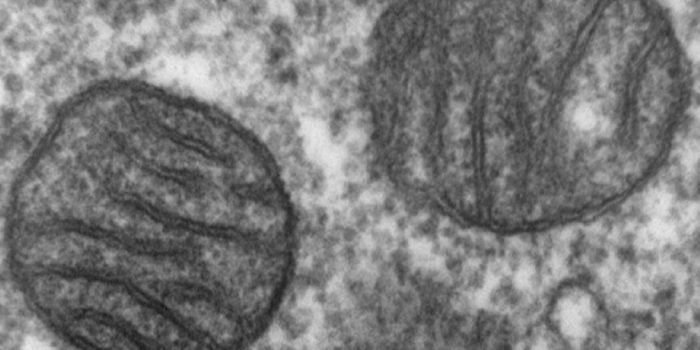

JUN 02, 2016Cell & Molecular BiologyMitochondrial replacement therapy was hailed as a promising new way to overcome diseases passed down in the DNA of mitoc ...